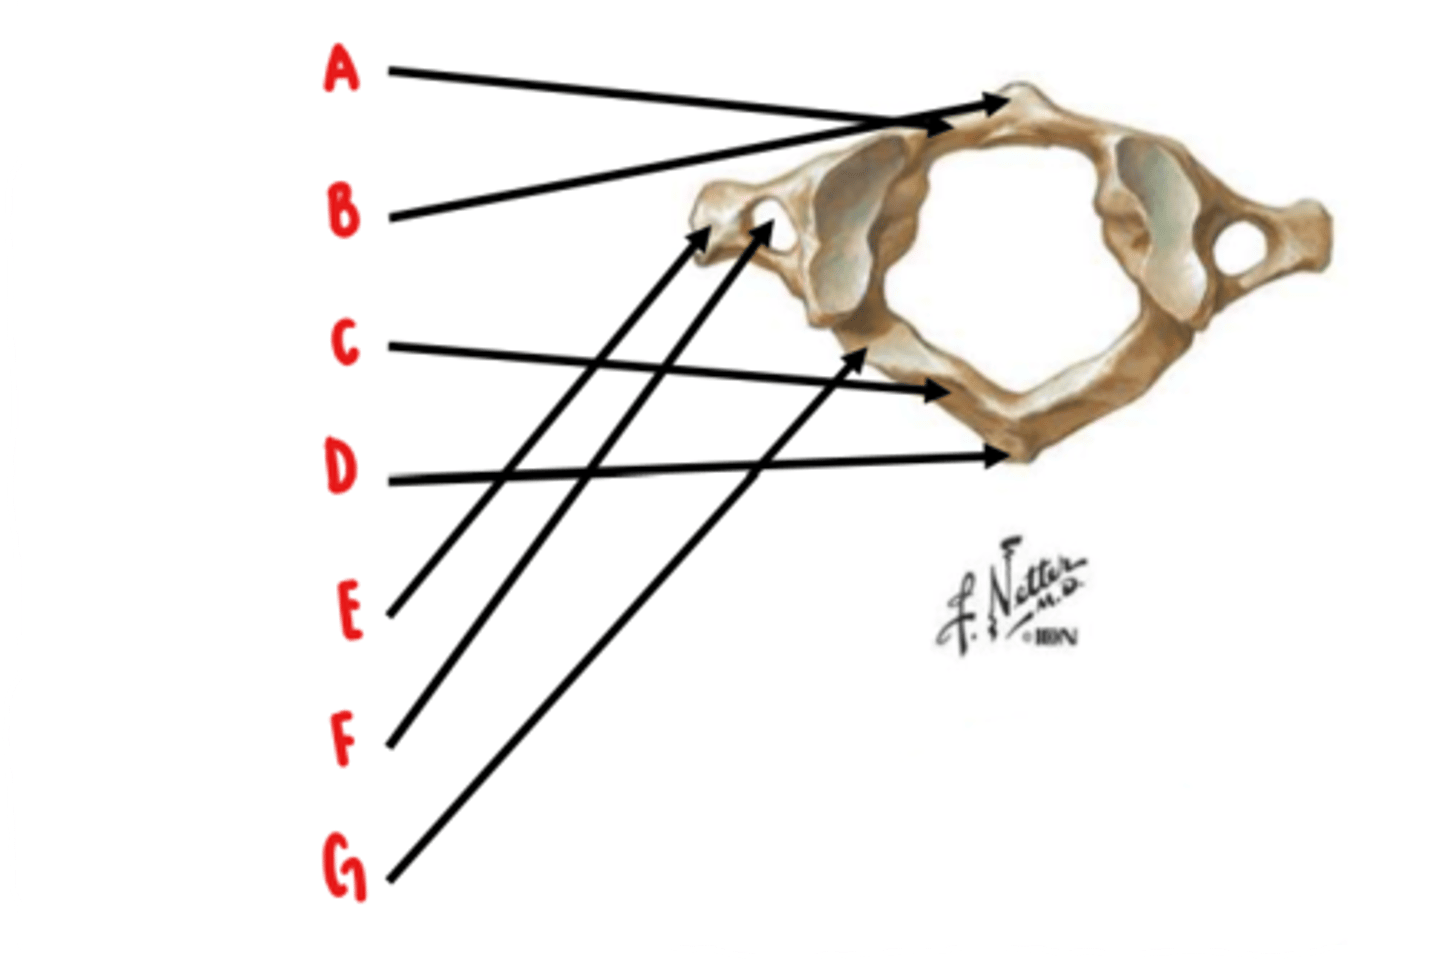

Atlas (C1)

What vertebrae is this?

anterior arch

Identify A

anterior tubercle

Identify B

posterior arch

Identify C

posterior tubercle

Identify D

transverse process

Identify E

transverse foramen

Identify F

groove for vertebral artery

Identify G